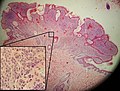

Micrograph of an intradermal melanocytic nevus